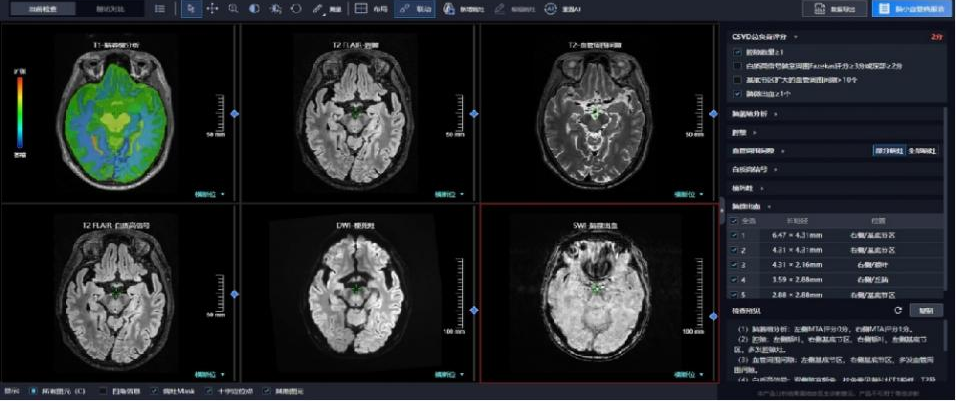

针对这一临床痛点,联影智能研发的脑小血管病AI人工智能诊断系统,以其精准、高效的特点,为脑小血管病的早期诊断、评估和治疗提供了新的可能。该系统是国内首个能够实现AI多序列同步阅片的脑小血管病AI人工智能诊断系统。并且,该脑小血管病AI人工智能诊断系统能够全方位自动评估脑小血管病的六大影像征象,包括脑白质高信号、近期皮质下小梗死、腔隙、血管周围间隙、脑微出血、脑萎缩等。

基于诊断结果,该脑小血管病AI人工智能诊断系统还能智能生成脑小血管病MR影像评估报告,为医生提供全面的诊疗依据。